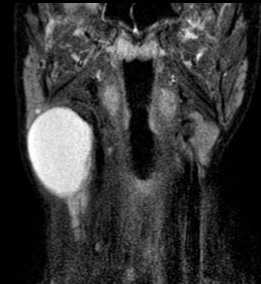

(Слева) STIR MPT, коронарная проекция (МР-нейрография). Асимметричное увеличение корешка CVIII нерва. выходящего между С7-Т1 позвонками.

(Справа) STIR MPT, коронарная проекция, другой пациент. Веретеннобразная шваннома с неоднородным гиперинтенсивным сигналом, расположенная в нижних отделах шеи. По сравнению с соседними нервами плечевого сплетения сигнал гораздо интенсивнее. При проведении тонкоигольной биопсии, благодаря которой удалось подтвердить диагноз, у пациента отмечалось подергивание руки.